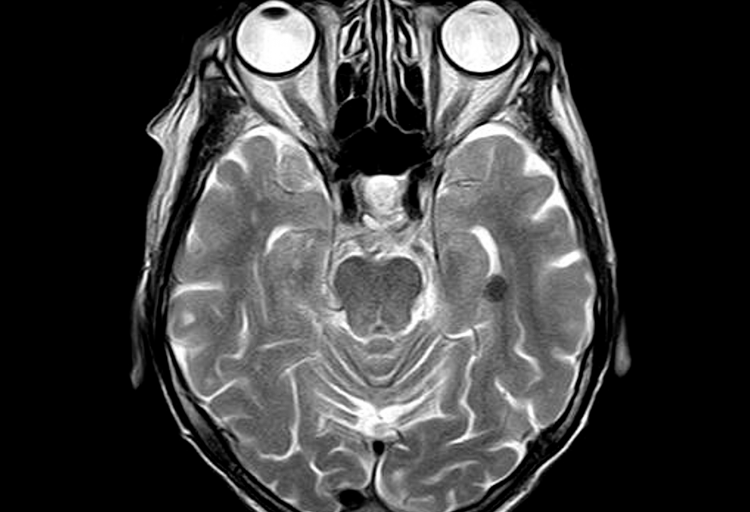

Wenn jemand von euch testen möchte, in welche Kategorie er fallen würde, der kann sich ja mal an folgendem Test versuchen:

Beim Embedded Figures Test geht es darum, aus einer überladenen Darstellung eine bestimmte Figur herauszufiltern. Menschen, die eher holistisch denken, sollten damit ihre Schwierigkeiten haben, da sie jede Bildinformation einbeziehen. Wie ist es bei euch? Findet ihr die Figur im Bild?

Und? wie lange habt ihr gebraucht? Habt ihr die Figur gefunden?

So. Nun habe ich Platz geschaffen, um euch die Lösung für den oben gezeigten Test zu liefern. Eine Variante könnte sein: